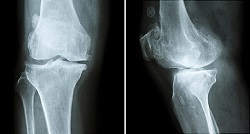

"شکستگی تنشی استخوان" به ترکهای ریز و کوچک روی استخوان گفته میشود که بر اثر فشارهای مکرر و اغلب از استفاده بیش از حد از استخوانها همچون بالا و پایین پریدن یا دویدنهای طولانی مدت ناشی میشود.

به گزارش ایسنا، همچنین در برخی مواقع استخوانی که استحکام خود را بر اثر بیماریهایی از جمله پوکی استخوان از دست داده با انجام عادیترین حرکات دچار شکستگی تنشی میشود.

این نوع از شکستگی بیشتر در استخوانهایی از بدن همچون پا و ساق پا مشاهده میشود که وزن بدن را تحمل میکنند و همچنین احتمال اینکه تمامی افراد شکستگی تنشی را تجربه کنند، وجود دارد.